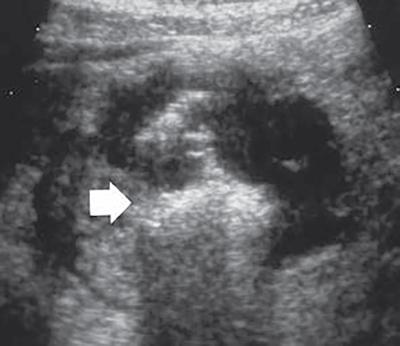

Ultrasonography (USG)